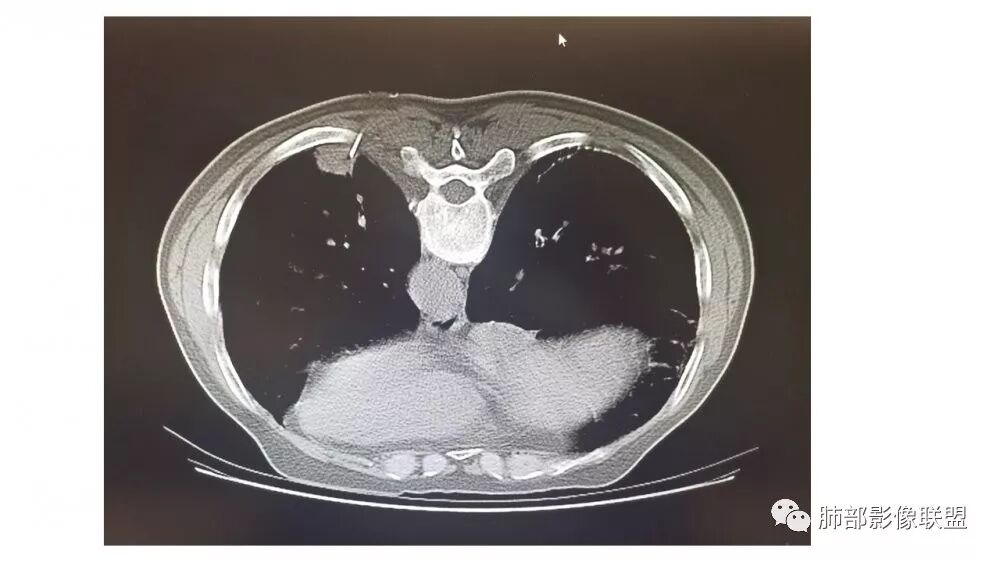

南边:糊墙,长轴与胸膜平行;边缘收缩+膨隆;脐凹征

常规:隐球菌与癌鉴别

脐凹征,高度提示恶性

因为其与胸膜的关系与右上叶的不一致,所以不能一元论

而且周围的表现不一致

还有就是间质性病变基础上,恶性变的几率很高